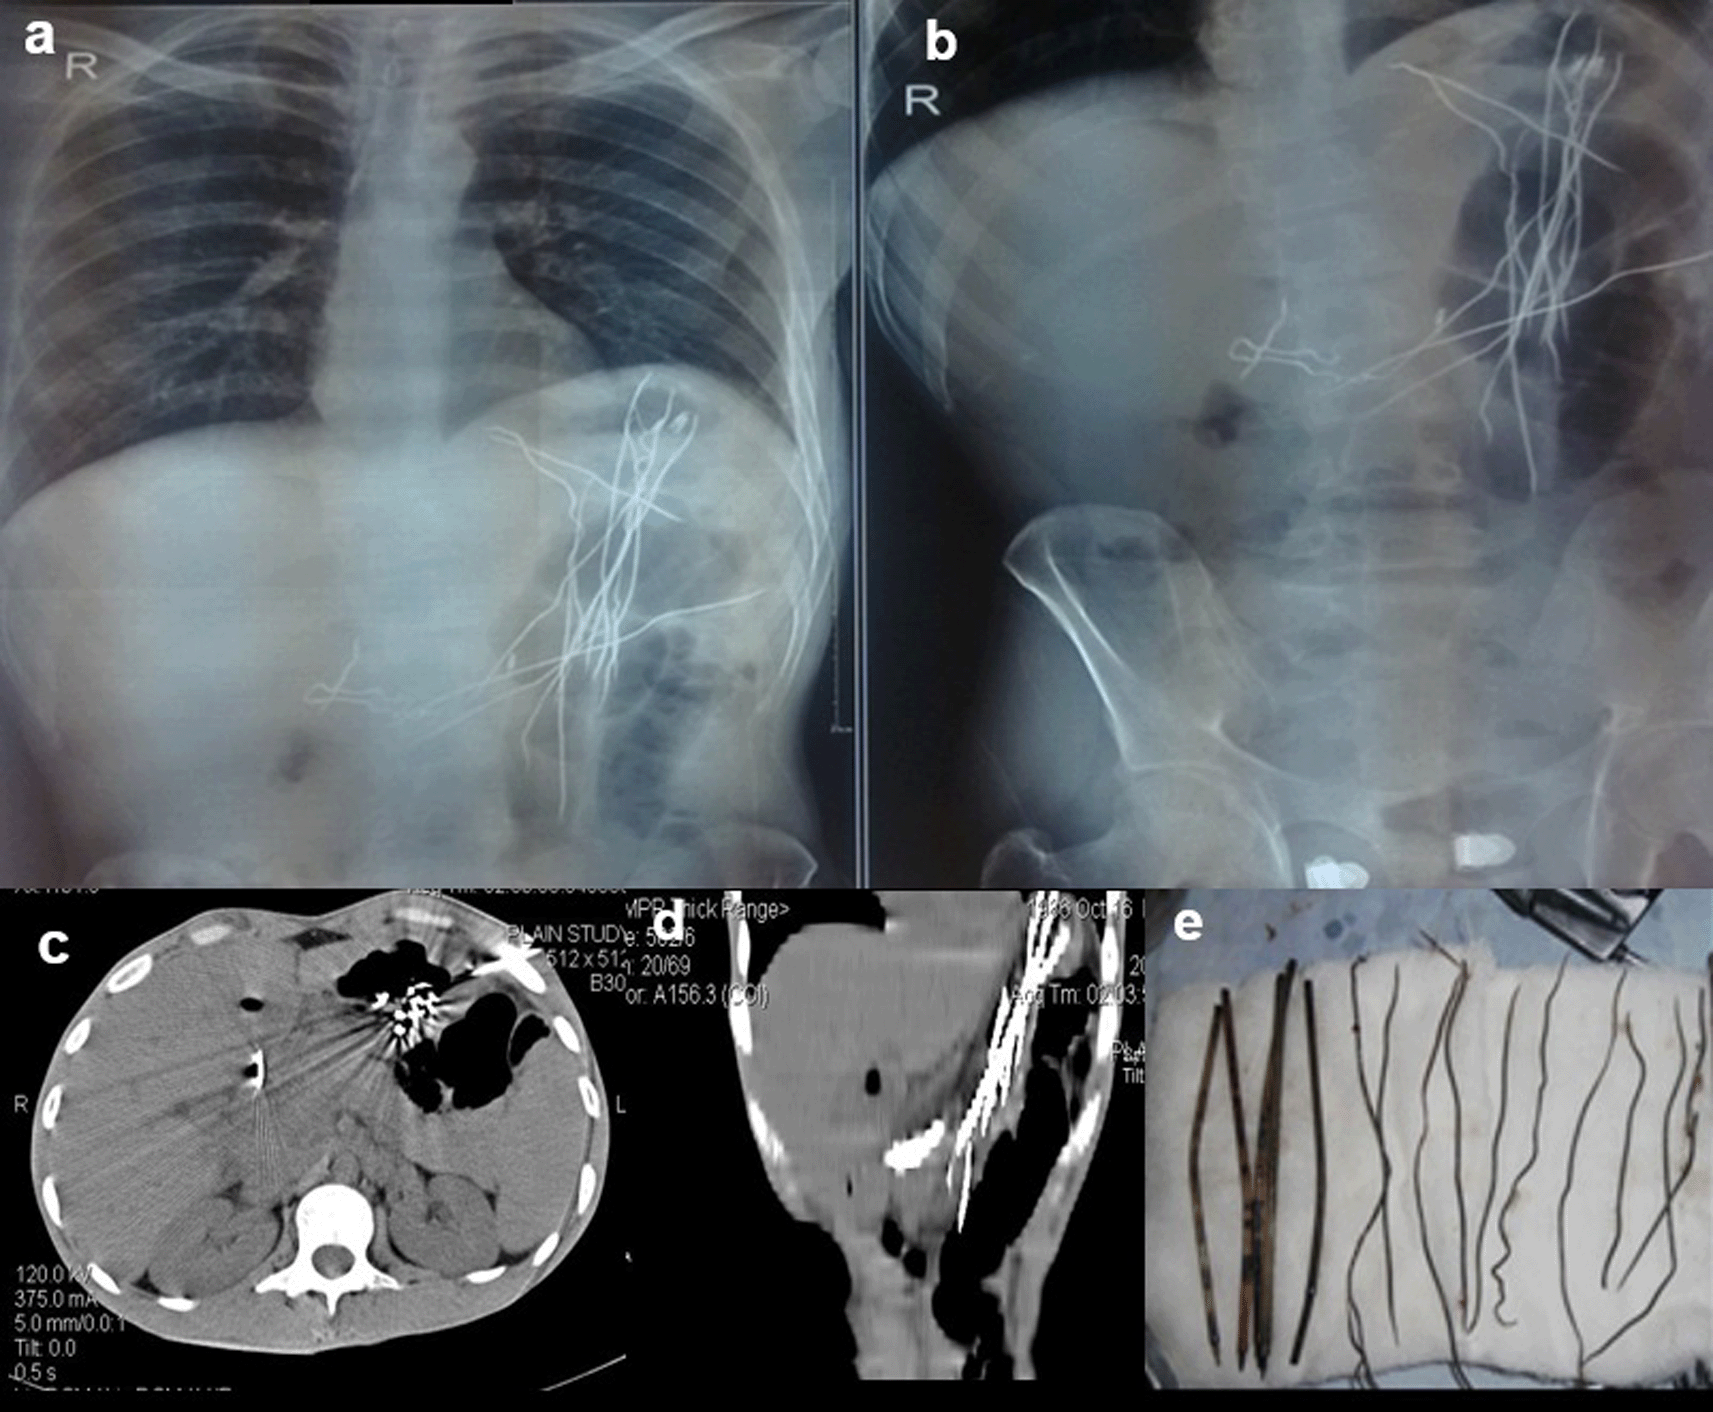

Case 3: A 25-year-old male patient came for ultrasound examination with complaints of pain in the abdomen for two-three months. On palpation of the abdomen, the patient had tenderness in the epigastric and periumbilical regions. The clinical examination of the rest of the systems was normal. Radiograph of the chest and abdomen reveal multiple linear radio-opacities in the left hypochondriac and lumbar quadrants of the abdomen, and a plain CT scan shows multiple hyperdense linear metallic foreign bodies within the gastric lumen, many piercing the gastric wall partially without any evidence of perforation. On laparoscopy, multiple refills of the pen and wires were found in the stomach, which were removed.

The swallowing of foreign bodies is a common condition in children and mentally challenged individuals.3–5 Fortunately, most ingested objects move through the digestive system without causing any problems (Figure 1a,b). Sharp and elongated objects can pass uneventfully (Figure 2a,b); however, they can pierce the mucosal lining and seriously damage or completely perforate the intestinal wall (Figure 3a-e). The object may just partially puncture the gut wall, resulting in a chronic inflammatory condition with few symptoms that is diagnosed months or years later.5–7

On laparoscopy, multiple refills of the pen and wires were found in the stomach, which were removed (e).

When a patient cannot provide a sufficient history or has swallowed things that are not naturally radio-opaque, the diagnosis of an ingested foreign body is frequently missed. If a foreign body is suspected and is not visible on a Radiograph because of its radiolucent nature, a CT scan of the abdomen or chest may be beneficial8 (Figure 4a,b).